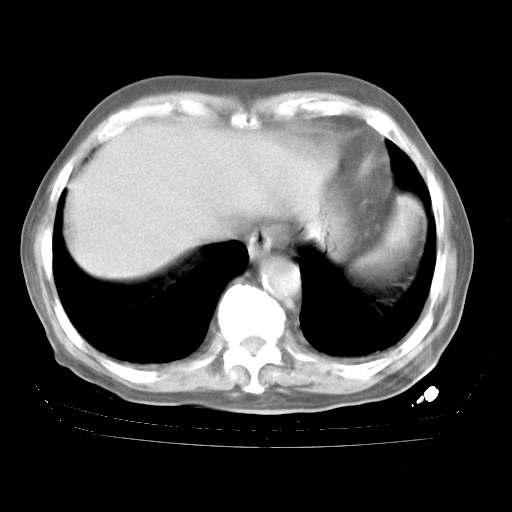

4月28日肺部CT

个人阅读4.14日肺部CT平扫:纵隔窗无异常,但肺窗示:双下肺内、后基底段有片絮状侵润影,部位以后基底段为著,以间质改变为主,呈急性肺泡炎征像,和首次住院影像学有相似之处。仅是个人读片,明日请相关专家再读片哈。其它建议同上。

1、108#的是4月14日的胸部CT(发此贴时还没看着28日的CT)。14日的胸部CT其实已经出现改变(如108#所述),个人认为28日的胸部CT除纵膈窗疑似有双侧胸膜增厚或少量胸积液(可行胸部B超明确)外,与4月14日对照病变有所加重;2、已经给予“异烟肼、利福平、乙胺丁醇”抗痨治疗?如果是,甲强龙80mg可缓慢减量;如果环磷酰胺已停用,暂不使用;3、中性粒细胞92%,明显升高,目前体温情况?注意合并细菌感染可能,使用左氧氟沙星情况下,是否联用B-内酰胺类抗菌药物?另外是查免疫全套非风湿全套。

今请临免主任会诊后认为:4月14日胸部CT已有双下肺间质性改变。患者病情复发多系激素减量过快不正规所致。目前甲强龙80mg/日,一周后酌情开始减量,不易过快。环磷酰胺若已停用,暂不使用。他同意目前抗菌药物使用,但应考虑是否加用B-内酰胺类抗菌药物(中性细胞明显增高);2、结核复发目前依据不足;3、若免疫全套各项指标正常,考虑多系特发性肺间质炎可能大。4、加强支持,并注意保护胃黏膜。